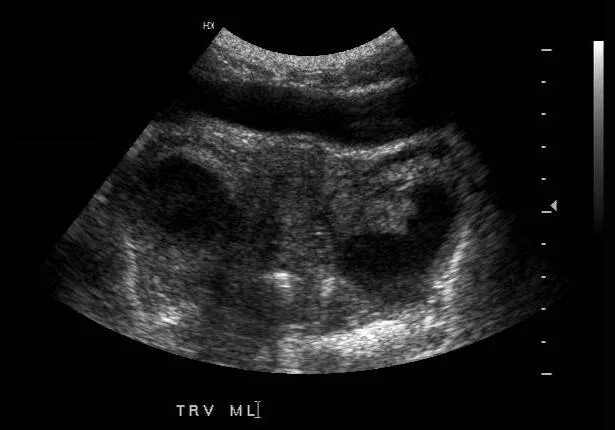

Трансабдоминальное узи